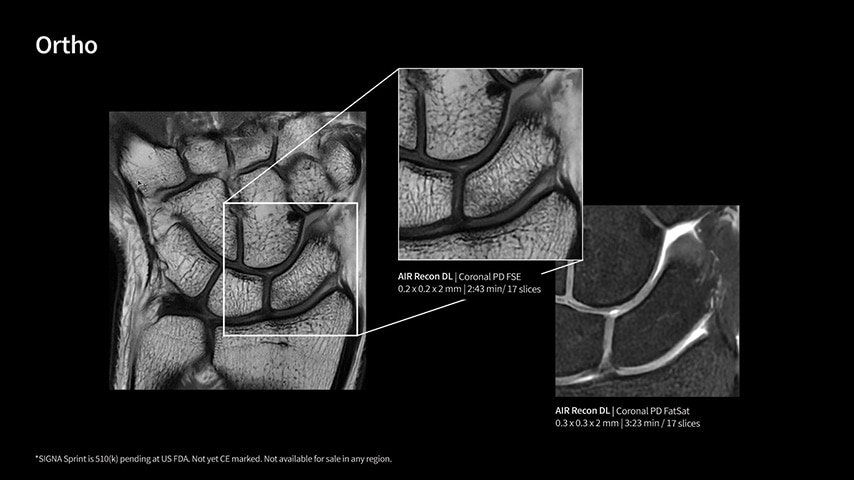

In oncological assessments, diffusion imaging is a critical clinical indicator. SIGNA Sprint offers clearer diffusion, reduced distortion, and improved SNR.¹

Within cardiovascular diseases, the functional assessment of the heart is an essential imaging application. SIGNA Sprint is powered by built-in AI technologies—Sonic DL™, AIR Recon DL and AIR x™—enabling high-quality imaging even in the most demanding anatomies.

Imaging capabilities to unlock the power to explore further

The growing clinical need within oncology and cardiology requires an MRI scanner that can rise to the challenge. With a high gradient performance of 65/200, SIGNA Sprint helps deliver crystal-clear imaging for ultimate diagnostic confidence. Improved signal-to-noise ratio (SNR) and diffusion, with deep-learning solutions that could enhance diagnostics and treatment response monitoring in your oncology patients.¹ Additionally, the shift from qualitative to quantitative cardiac MRI reduces the time and expertise needed to interpret scans and offers greater consistency and reliability. Helping you to unlock the power to explore further - even in your most challenging cases.

With GE HealthCare's comprehensive suite of deep-learning solutions integrated into SIGNA Sprint, you can unlock the full potential of your MRI system. No need for complicated patient setups or imaging protocols. The exceptional intelligence of our AI solutions offer multiple benefits, with AIR Recon DL giving pin-sharp images, Sonic DL accelerating scans up to 12x, and AIR x enabling automated slice placement. All helping to enhance your department’s workflow efficiency, increase patient throughput, and get the diagnostic clarity you need, faster.¹ Meaning you can spend more time on what truly matters—personalized patient care, enabling optimized treatment plans and treatment response monitoring—ultimately, supporting better clinical outcomes.